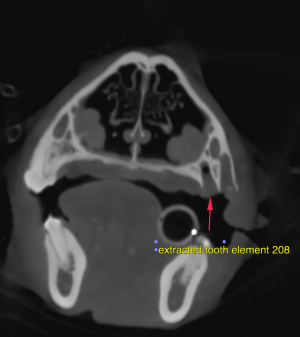

The tooth element 208 is absent and small gas bubbles are noted in the respective empty alveolar crests. The overlying soft tissues at this level present mild irregular margins. The nasal cavity presents the expected aerated spaces between thin & even conchae and turbinates with smooth mucosal lining. The nasal bones are within normal limits. The nasal passages are patent. There is no evidence of a mass lesion or rhinitis. The frontal sinuses are aerated and within normal limits.

No evidence of a nasal mass lesion or rhinitis

Current state after complete tooth extraction triad 208. If clinical signs persist consider rhinoscopy for further evaluation.